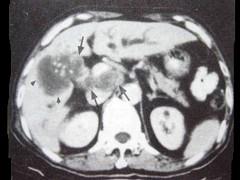

问题 男,68岁,上腹部隐痛二月余,CT检查如图,最可能的诊断是()

选项 A.慢性胆囊炎 B.胆囊癌(肿块型) C.胆囊腺肌增生症 D.胆囊息肉 E.胆囊区转移瘤

答案 B